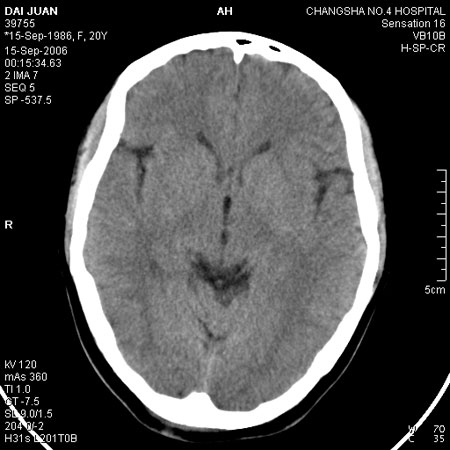

请问各位战友:图示箭头处是否为颅骨骨折?

病史:患者,女,20岁.头部及腹部外伤20分钟.伤后昏迷,无呕吐.头及右侧腰背部疼痛,双侧瞳孔等大,

右肾区叩痛.其它无异常.患者家属否认原有外伤史.

请大家看看是否为颅骨骨折.还是正常变异,或为陈旧骨折.谢谢.

图片未上传完,所见图象示枕骨线样低密度影,边缘锐利,结合外伤史,伤后昏迷,骨折不能除外。

枕骨的线样低密度影锐利、清晰,但正好位于矢状缝的位置,局部无明显软组织肿块,相临及对冲部位脑实质亦无出血及挫裂伤表现。

单就这几层暂不考虑骨折,建议上传完整图片。

楼主所关心的另一个线样影应该是头颅矢状面略偏左,射线正好穿过所致,不需要考虑骨折。

枕骨是单块的,矢状缝是在顶骨而不是在枕骨,枕骨后缘见线状低密度,边缘税利,考虑在骨折存在。

枕部考虑骨折。一般的颅逢不会跨越板障,楼主所示枕骨断面两侧板障也不连续。